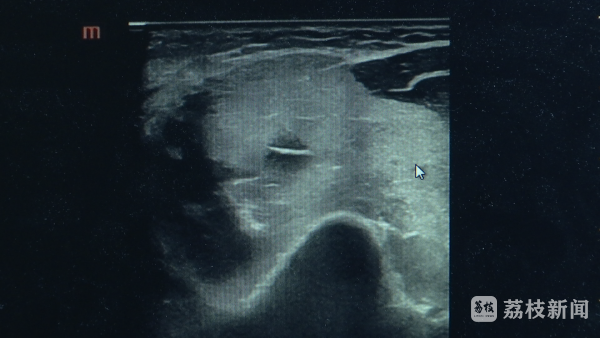

梅雨季降临开yun体育网,高温高湿的天气里,健身一定要科学、适量。最近,南京又名小伙去健身房检修,一通猛练,导致了横纹肌融化详尽征。 6月17日傍晚,南京市中西医聚拢病院接诊了又名23岁的小伙,他说我方最近每每考验上肢,肌肉拉伤了,但接诊医师发现了终点。 南京市中西医聚拢病院超声科副主任医师李亚洲先容,进行超声查验的技艺就发现,肩部上肢的肌肉日常地肿胀,回声纹理污秽不清,和正常的一看就不通常,因为它的范围相比广,B超看了之后就怀疑这个病横纹肌融化详尽征。 小伙嗅觉我方精神景象可以,查验完就准备回家了,医师反复和他疏导,但愿再验个血液生化查验。这一查不得了,肌酸激酶飙升到了正常值的150倍! 当今,患者正在进一步调治。医师先容,横纹肌融化详尽征,是由于某些成分形成骨骼肌细胞被破碎,开释广宽的肌红卵白和肌酸磷酸激酶等物资到血液里,并瓦解成某些有毒物资,它们可能堵塞肾组织导致肾衰。 南京市中西医聚拢病院体卫和会畅通医学门诊 副主任中医师王金勇,除了是一个广宽的单一畅通会导致之外,另外皮高温高湿的这种容易中暑的天气,容易发生这种横纹肌融化征,有1/3阁下的横纹肌融化征东说念主会发生急性的(肾)缺少,可能会导致暴毙的存在。许多东说念主在畅通明,也会出现肌肉酸痛。那么若何差异我方的是普通的肌肉酸痛如故横纹肌融化征呢? 王金勇强调,横纹肌融化详尽征 临床上有个三个指征,一个是乏力,一个是肌肉酸痛,还有一个是深色小便省略黑茶色小便。延伸性肌肉酸痛,它是一个酸痛为主,24小时以后它放浪就会镌汰了 这种酸痛的嗅觉,它基本上来说不动 它不会太痛,横纹肌融化详尽征不是的,横纹肌融化详尽征一朝发生以后,它这种疾苦这种胀痛这种酸痛它是放浪加剧的,另外还有说它不畅通它也疼。 |